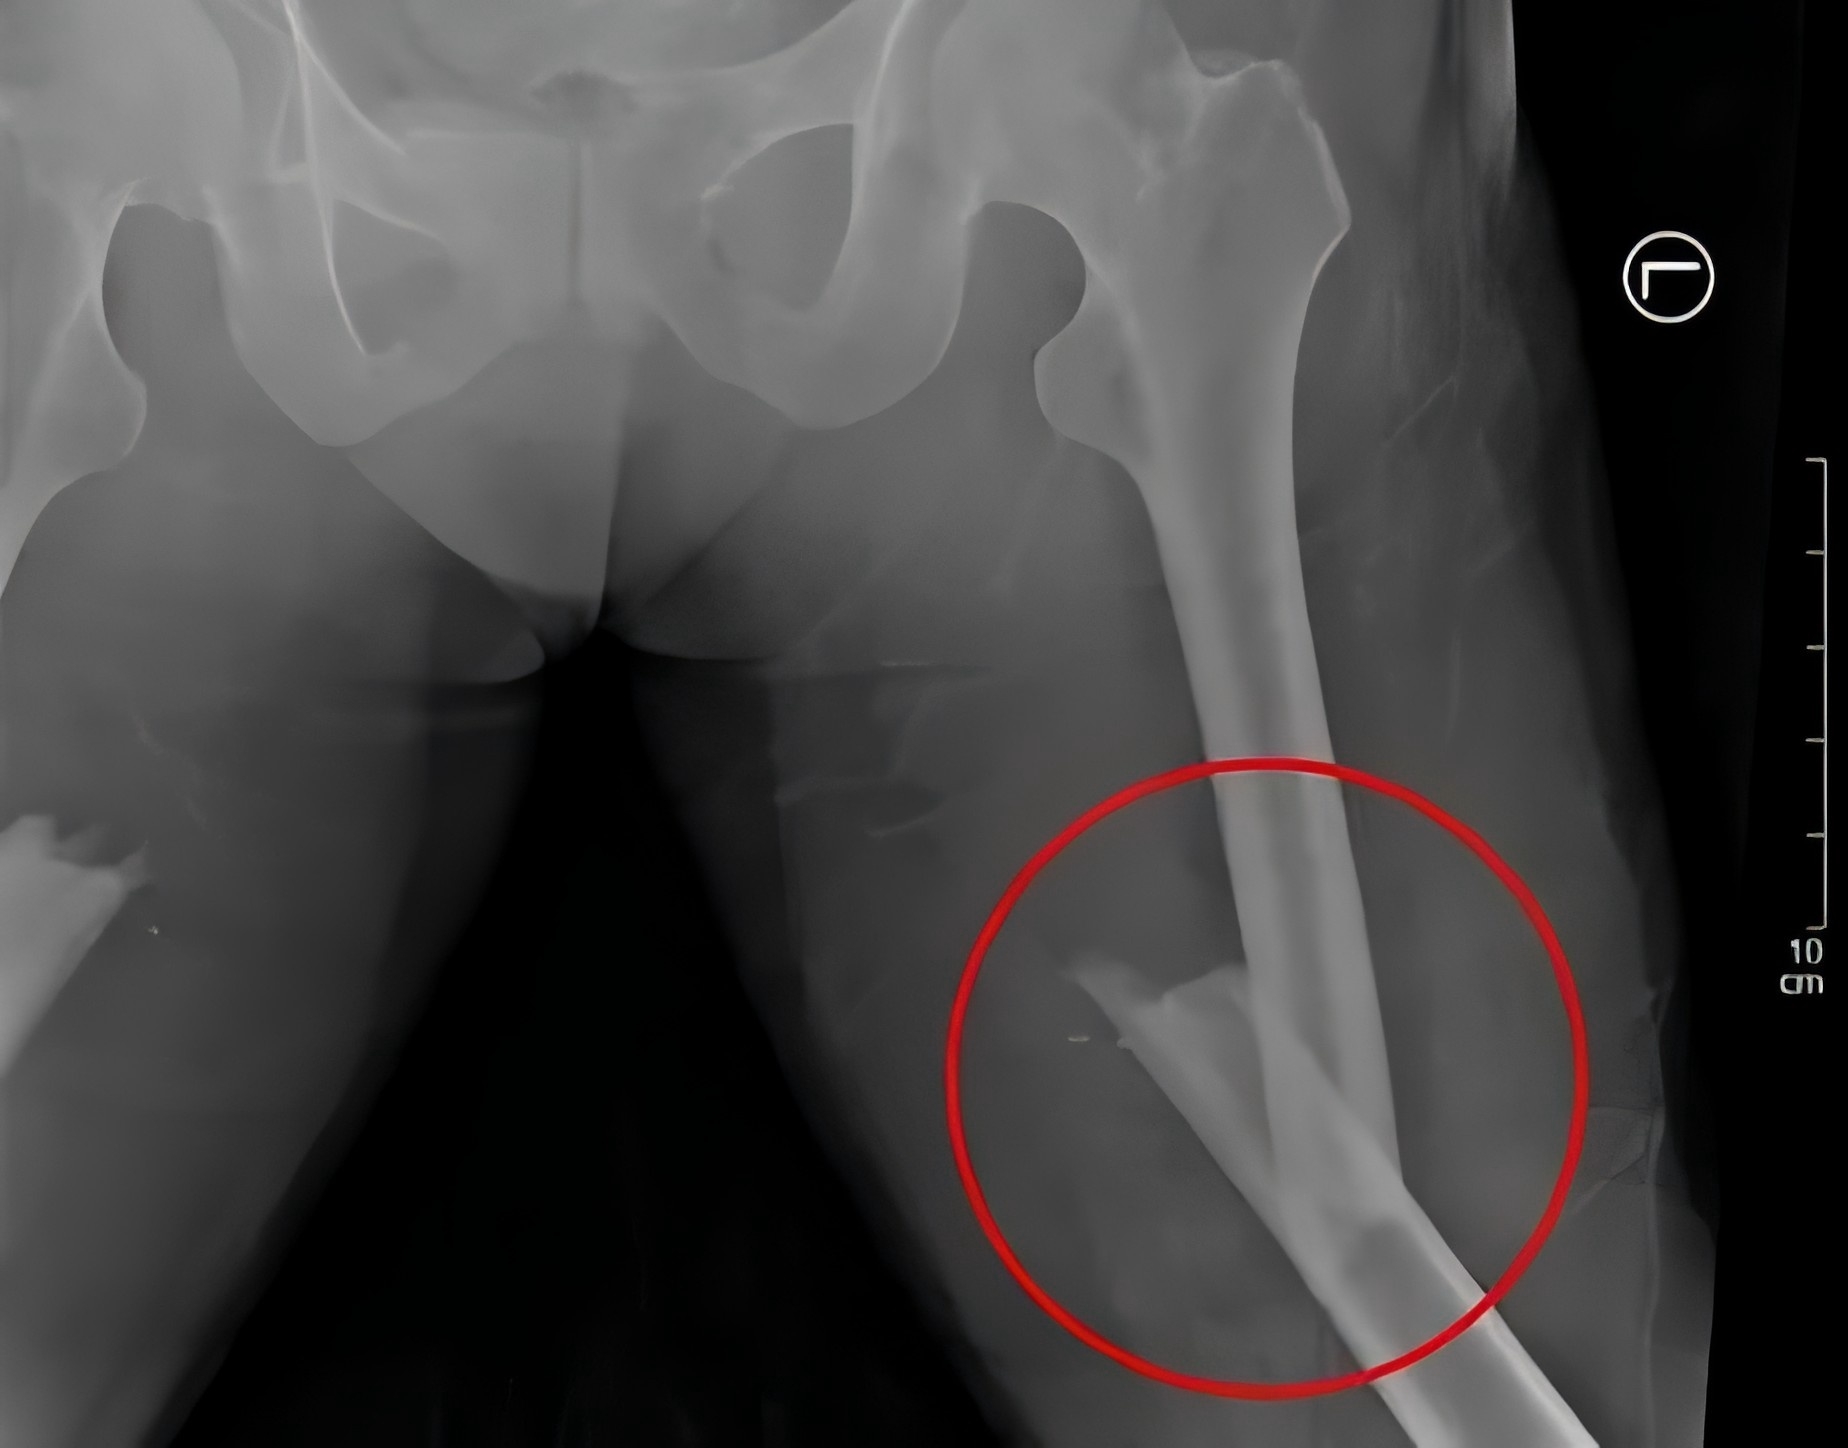

2月28日,48歲的戴某不慎被重物(重量約為2噸)砸傷,導致多發性骨盆骨折、右側粉碎性髂骨骨折、雙側股骨骨折、右側腓骨骨折等多處損傷,尤其是骨盆處幾乎“散架”,患者失血性休克,生命垂危。

殷小軍團隊基于損傷控制理念,為患者量身定制了微創手術方案。手術分為兩期進行:待患者生命體征穩定后,一期先行骨盆及一側股骨骨折微創內固定治療;二期行另一側股骨骨折微創內固定手術。

(患者術后X片)